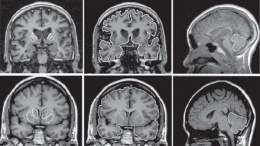

Se dice que es una enfermedad neurológica pues afecta al cerebro, a áreas determinadas de éste, donde las neuronas (células cerebrales), van degenerándose y finalmente mueren. Recibe este nombre pues fue descrita en primer lugar por George Huntington, en 1872, aunque es también conocida por Corea, (en griego danza) debido al movimiento característico de esta enfermedad. Durante mucho tiempo se la ha estado llamando El mal de San Vito.

Sus síntomas suelen aparecer hacia la mitad de la vida de la persona que lo padece (unos 30 o 50 años de media) aunque pueden aparecer antes y los pacientes muestran Degeneración neuronal constante, progresiva e ininterrumpida hasta el final de la enfermedad que suele coincidir con el final de su vida por demencia y muerte o suicidio. Esta enfermedad genética presenta una herencia autosómica dominante, lo cual significa que cualquier niño en una familia en la cual uno de los progenitores esté afectado, tiene un 50% de probabilidades de heredar la mutación que causa la enfermedad. La enfermedad produce alteración cognoscitiva, psiquiátrica y motora, de progresión muy lenta, durante un periodo de 15 a 20 años. El rasgo externo más asociado a la enfermedad es el movimiento exagerado de las extremidades (movimientos coréicos) y la aparición de muecas repentinas.

Además, se hace progresivamente difícil el hablar y el tragar. En las etapas finales de la enfermedad, la duración de los movimientos se alarga, manteniendo los miembros en posiciones complicadas y dolorosas durante un tiempo que puede prolongarse hasta horas. No obstante, los trastornos psíquicos graves, que anteceden normalmente a los musculares, son los rasgos característicos de la enfermedad. Ésta puede desencadenar episodios depresivos reiterados con repercusiones negativas en el entorno de allegados. Las facultades cognitivas disminuyen, así como la memoria, y la capacidad de concentración empeora. La enfermedad termina en una demencia fuerte, que puede conllevar deseos de suicidio.